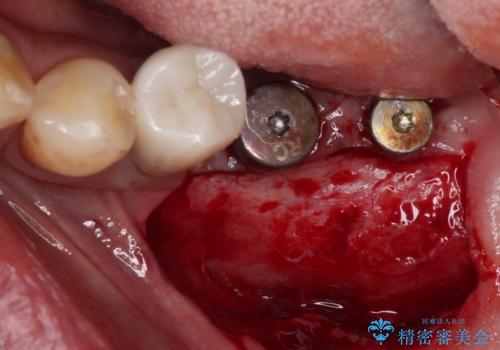

インプラント埋入後、手前のインプラント周りの丈夫な歯肉(角化歯肉)が失われてしまったため、角化歯肉の移植を行うこととなりました。

十分な角化歯肉が獲得でき、清掃性の高い環境が達成されました。